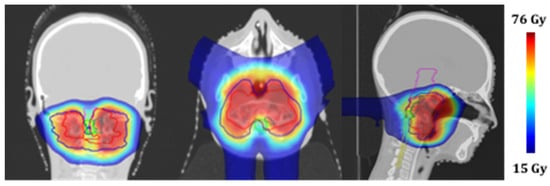

A computed tomography (CT) scan of the patient in supine position was acquired. To guarantee the immobilization and reproducibility of the patient position on the treatment couch, a thermoplastic mask coupled with a customized cushion made of a dedicated foam-like material was used. The CT scan and the pre-treatment MRI images were registered to help the clinician to identify the structures of interest. The clinician used the CT images to define the target volume and OARs to be spared. The treatment plan was then prepared using a commercial treatment planning system (Elekta XIO) equipped with a pencil beam dose calculation algorithm. A 3-field (1 posterior and 2 anterior-oblique) plan was created using a single-field-optimization technique [14]. The total prescription dose for the target was 73.8 GyRBE, delivered in 41 fractions (1.8 GyRBE per fraction, 5 fractions a week), while the main constraints (expressed as allowed dose to 1% of the volume) were set for the brainstem and spinal cord at 54 GyRBE and 50 GyRBE, respectively. The treatment was delivered in a proton therapy gantry room featuring a pencil beam active scanning technique. The Figure 3 shows the planned dose distributions on the CT scan.

The following contours are reported: planning target volume 0–54 GyRBE (blue), planning target volume 54–73.4 GyRBE (red), nodule component (green), brainstem (purple), and spinal cord (yellow).

Figure 3. Treatment planning: proton dose distributions in coronal, axial and sagittal views.